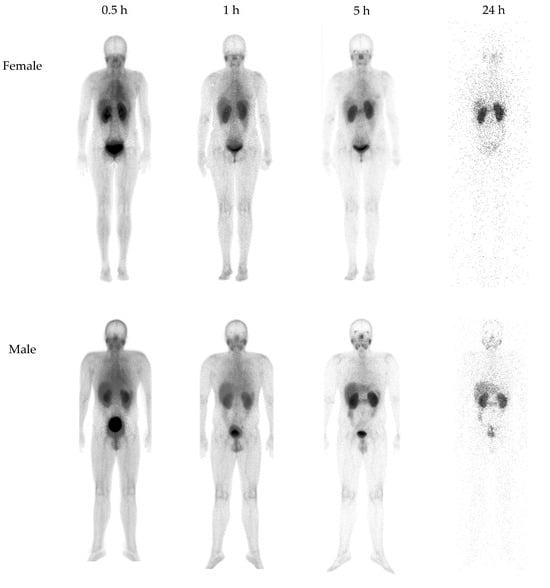

3.2.1. Biokinetics and Dosimetry